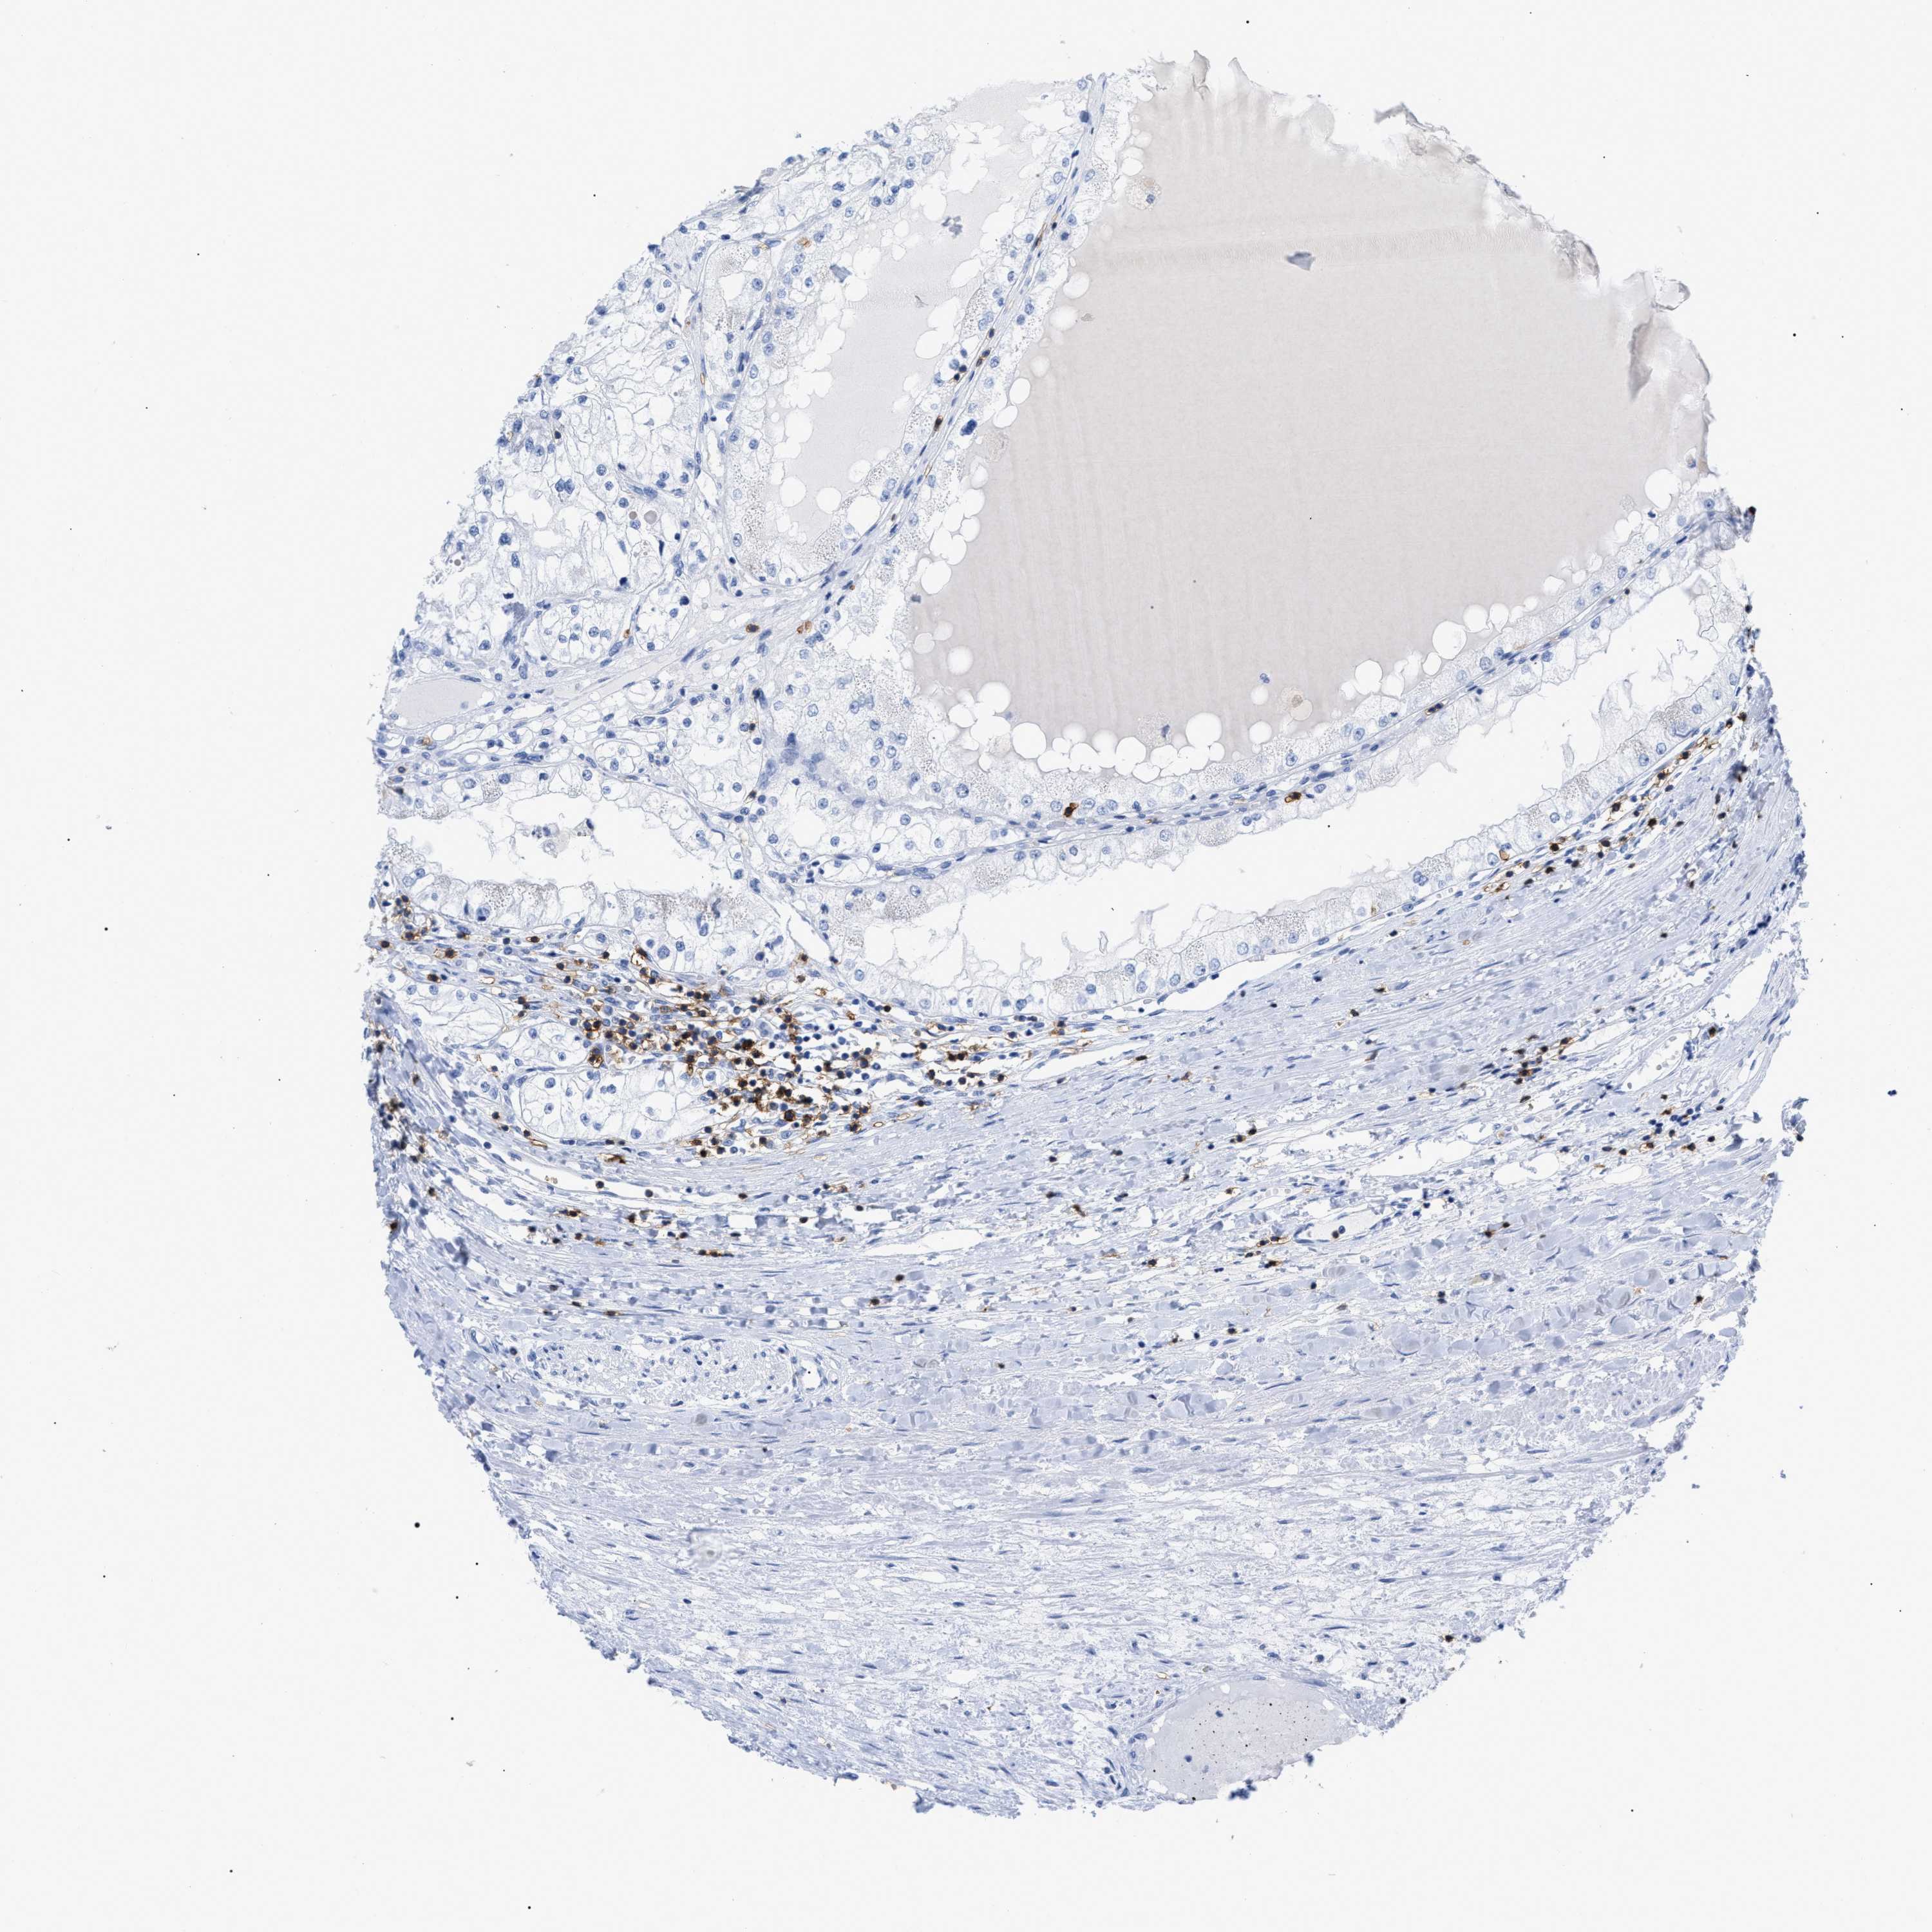

KIDNEY RENAL PAPILLARY CELL CARCINOMA (TCGA) - Interactive survival scatter ploti

The Survival Scatter plot shows the clinical status (i.e. dead or alive) for all individuals in the patient cohort, based on the same data that underlies the corresponding Kaplan-Meier plots. Patients that are alive at last time for follow-up are shown in blue and patients who have died during the study are shown in red.

The x-axis shows the expression levels (FPKM) of the investigated gene in the tumor tissue at the time of diagnosis. The y-axis shows the follow-up time after diagnosis (years). Both axes are complimented with kernel density curves demonstrating the data density over the axes. The top density plot shows the expression levels (FPKM) distribution among dead (red) and alive patients (blue). The right density plot shows the data density of the survived years of dead patients with high and low expression levels respectively, stratified using the cutoff indicated by the vertical dashed line through the Survival Scatter plot. This cutoff is automatically defined based on the FPKM cutoff that minimizes the p-score. The cutoff can be changed by dragging the vertical line or by entering a cutoff value in the square labeled "Current cut-off".

Under the Survival Scatter plot the p-score landscape (black curve; left axis) is shown together with dead median separation (red curve; right axis). Dead median separation is the difference in median mRNA expression between patients who have died with high and low expression, respectively. It is calculated as follows: median FPKM expression of dead patients with high expression - median FPKM expression of dead patients with low expression. This is intended to aid the user in visually exploring custom cutoffs and the associated p-scores and dead median separation.

Individual patient data is displayed and can be filtered by clicking on one or more of the category buttons on the top of the page. Categories describing expression level and patient information include: high, low, alive, dead, female, male and tumor stages. The scale of the x-axis can be toggled between linear and log-scale by clicking on the "x log" button. Mouse-over function shows TCGA ID, patient information and mRNA expression (FPKM) for each patient.

& Survival analysisi

Kaplan-Meier plots summarize results from analysis of correlation between mRNA expression level and patient survival. Patients were divided based on level of expression into one of the two groups "low" (under cut off) or "high" (over cut off). X-axis shows time for survival (years) and y-axis shows the probability of survival, where 1.0 corresponds to 100 percent.

CD5 is not prognostic in Kidney Renal Papillary Cell Carcinoma (TCGA)

: 2.35